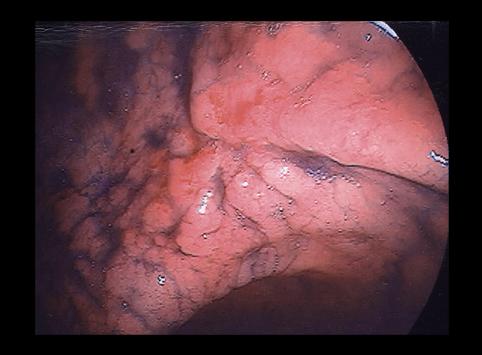

疾病(病理主体)的分类恶性上皮性肿瘤/印戒细胞癌

部位(按器官分)胃(部位)/胃角

检查方法内窥镜

肿瘤的肉眼分类0型(表在型)/IIc型(IIc+III)

肿瘤最大直径20~24

肿瘤的深度m